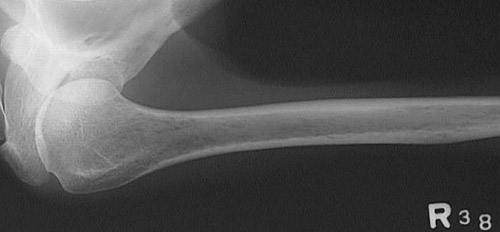

The humerus seen here with the shoulder at the left demonstrates severe osteoporosis with marked loss of bone density. In the humerus, there are even small 1 to 3 mm areas of

greater lucency

.